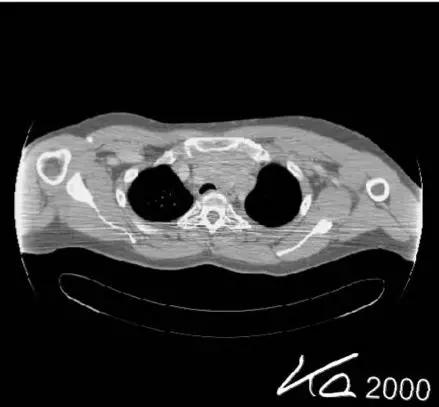

射线束硬化伪影:X线管发出的X线束是具有不同能量的连续的光谱,通过物体后光子能量的改变由该物质的衰减系数决定,而有效能量转移到高值一端的现象,称为“射线束硬化效应”。射线束硬化效应” 如果不能有效补偿,将会在图像中央产生环状或条状暗影。 抑制的方法是在焦点侧采取预滤过、软件校订。

(射线束硬化效应)